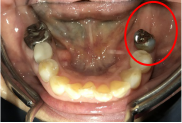

ブリッジの奥に伸びていた部分を削り取り、インプラントを2本入れました。

Before

青丸の部分を削り取りました